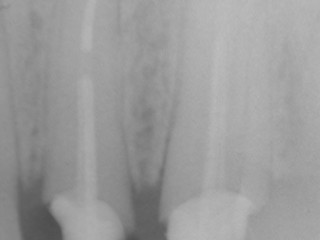

La cura consiste nell’isolare il dente con la diga (vedi articolo dedicato), rimuovere la polpa “morta” o il materiale inserito con la vecchia cura, dare una forma adeguata al canale, lavarlo con opportune sostanze disinfettanti per un tempo adeguato (almeno 30 minuti complessivi), sigillare il canale con un materiale stabile nel tempo e quindi procedere ad una adeguata ricostruzione del dente, sia con otturazioni che con eventuali corone protesiche (chi vuole approfondire veda l’articolo sull’endodonzia, qui o sul mio sito www.attiliovenerucci.it ).

A questo punto inizia il processo di guarigione che, nei controlli successivi, consentirà di verificare (in una alta percentuale di casi) che l’osso si è riformato e il granuloma è sparito.